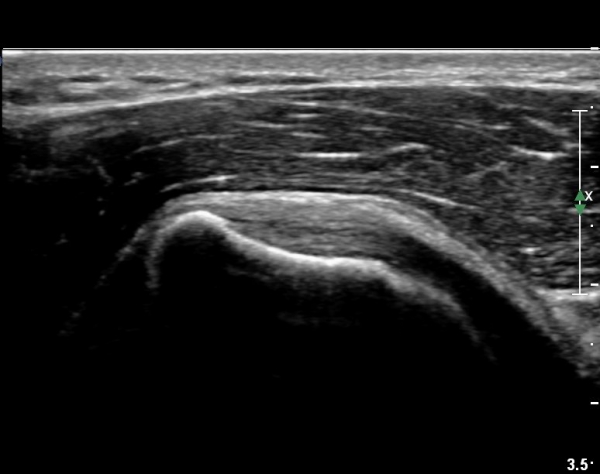

°ß°©ÇÏ±Ù°Ç ÁߺΠÁ¾´Ü¸é°Ë»ç¿¡¼­ ƯÀÌ ¼Ò°ßÀ» º¸ÀÌÁö ¾ÊÀ¸³ª(»çÁø 2) ŽÃËÀÚ¸¦ Á¶±Ý ÇϹæ(´Ù¸®ÂÊ)

À¸·Î À̵¿ÇÏ´Ï °ß°©Çϱٰdz»  ¼®È¸È­ µ¢¾î¸®°¡ °üÂûµÈ´Ù(»çÁø 3).